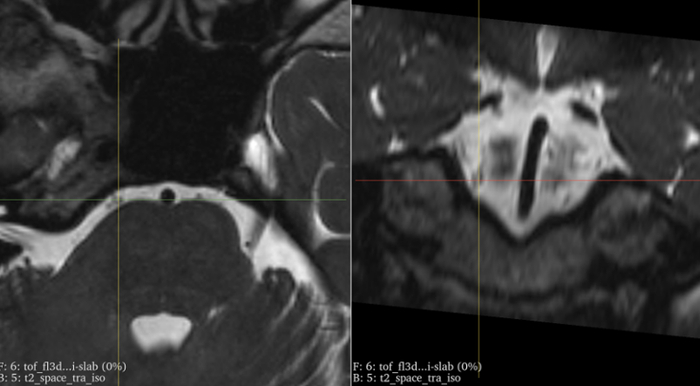

随后,这名女子来到上海交通大学医学院附属新华医院神经外科李世亭教授门诊,经外展神经薄分层核磁共振扫描这一影像学检查发现,她的右侧小脑前下动脉明显压迫右侧外展神经,导致外展神经出现 “短路” 。

患者的外展神经薄层磁共振检查提示:右侧外展神经受压。上海新华医院 供图